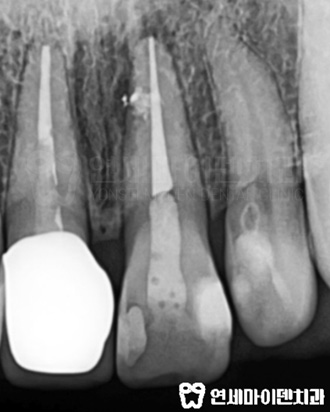

깨끗하게 내부 치료를 다시 하고 재감염이 없도록 레진코어까지 제대로 마무리했습니다.

앞니 재치료가 마무리 되었습니다.